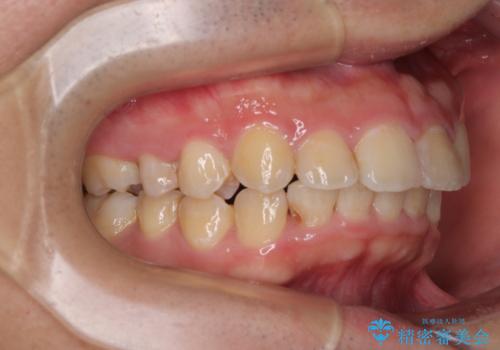

- デコボコと奥歯の咬み合わせのズレを気にして来院された患者様です。

骨格的に、下顎が右側にずれており、左側の咬み合わせに鋏状咬合などのアンバランスが生じている状態でした。

また、上顎前歯に欠損が1本あり、上下ともに前歯部に叢生が認められ、下顎前歯の大半が隠れてしまうほどの過蓋咬合も認められました。

咬合平面を平坦にしながら前歯の咬み合わせを挙上し、デコボコと鋏状咬合も改善していくこととしました。

骨格的な左右差が大きかったため、上下の正中のズレや、左右奥歯の咬み合わせなどは妥協的な仕上がりとなりました。

骨格的なズレに対応するにはワイヤー矯正が至適であり、マウスピース矯正は選択しないようにお話をしました。